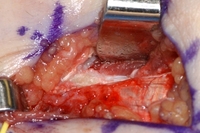

Surgery for refractory medial epicondylitis: pick-ups lifting off area of degenerative tendon after elliptical incision to excise this area

From the collection of Dr Brian Fitzgerald, Naval Medical Center San Diego, CA; used with permission